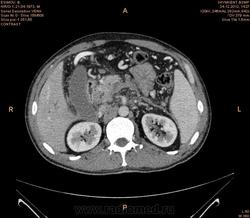

Предварительно образование головки ПЖ, и в печени. Что с ферментами?

на операций рак головки подж.железы с метастазир. печень.

инфильтрация тут нисходящей 12 перст кишки , расширенного холедох,расширенный вирсунгов проток ,нижная граница очень близко прилежит к нижней полой вене с правой почечной веной ,но четко визуализирутся передний листок фасции Героты(нельзя исключить ее инфильтрацию), инфильтрация конгломератом увеличенных лимфатических узлов ворот печени портальной вены с варикозным расширением вен, на вышележащий срезах четко определяются верхняя брыжеечная вена и артерия ,не хватает срезов для полной визуализации(помогли бы мпр),инфильтрирована восходящая ободочная кишка,конгломерат лимфат узлов за головкой поджелудочной железы в виде гиподенсивного участка вытянутой формы , ,мтс в печень,парааортальные